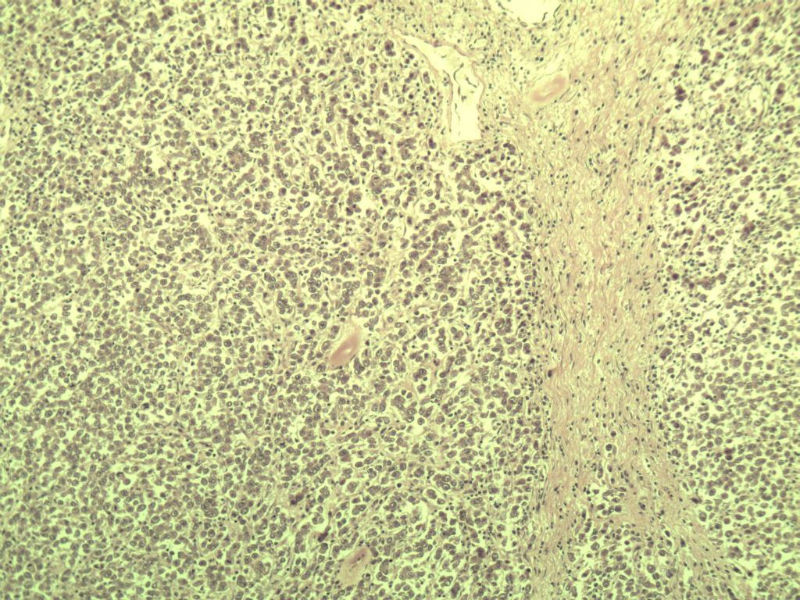

男 27岁 腹腔隐睾 5*3*2 cm, 切面灰红灰黄、实性、质中,请各位老师看看,是精原细胞瘤吗?感觉不像.腹腔隐睾图1

典型的精原细胞瘤,隐睾易恶变